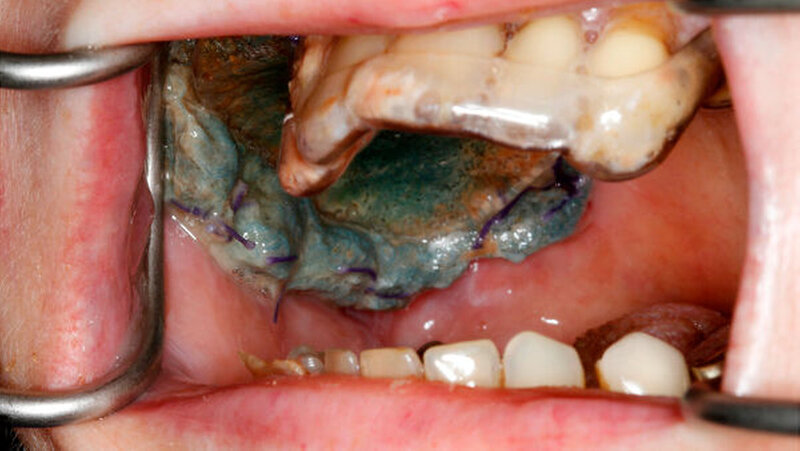

Bislang mussten orale Wunden und Defekte nach chirurgischen Eingriffen ab einer bestimmten Größe mit Kompressen abgedeckt oder mit einem eigenen Transplantat - mit oft aufwendiger Nahttechnik - versorgt werden. Die Wundabdeckung mit Kollagenmembranen, die lasergestützt an der Schleimhaut befestigt werden, ist dagegen eine neue Lösung.

Wehners Team arbeitet gerade daran, das Verfahren so anzupassen, dass es auch an der Mundschleimhaut einsetzt werden kann. Die Herausforderung sei, den Wärmeeffekt in der Tiefe des Gewebes zu minimieren, um möglichst wenig Wärmeenergie in die Haut- oder Schleimhaut bringen. Die Forscher wollen eine Membran entwickeln, die die Abdeckung der Wunde gewährleistet. Zudem muss der Proteinkleber so lange halten, bis sich das Gewebe regeneriert hat.

Damit der Laser speziell im Bereich der Mund-, Kiefer-, Gesichts- und Oralchirurgie eingesetzt werden kann, wurde ein Handstück konstruiert, in dem eine Faser zum Transport der Laserstrahlung sowie außerdem Fasern zur Detektion eines Temperatursignals und weiterer optischer Signale integriert sind. Dadurch wird gewährleistet, dass der Arzt den zulässigen Temperaturbereich einhalten kann und das behandelte Gewebe unbeschadet bleibt.